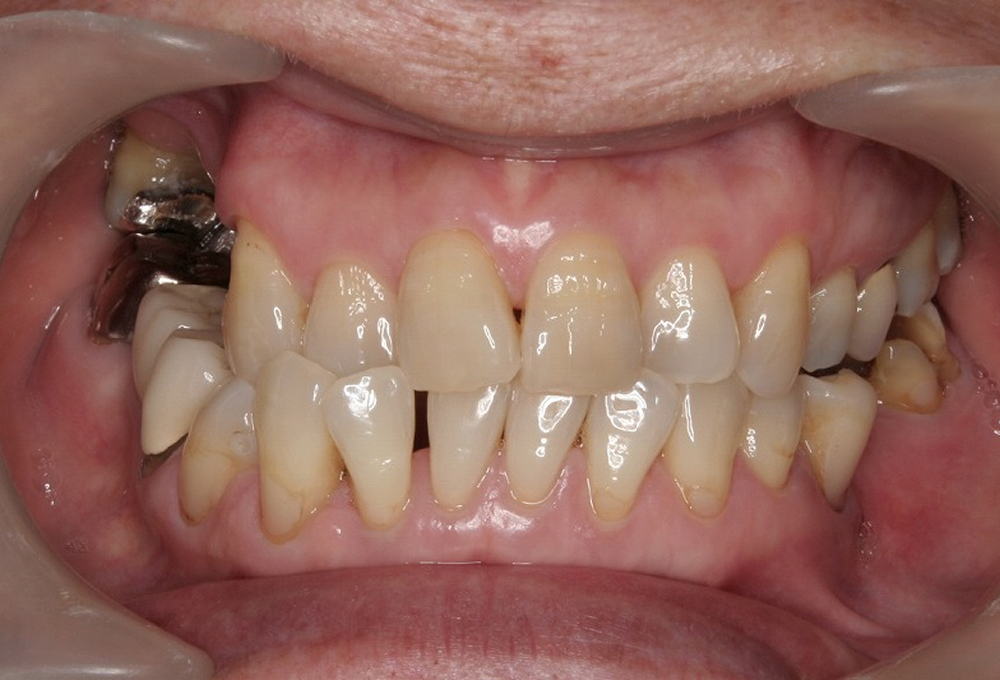

①術前